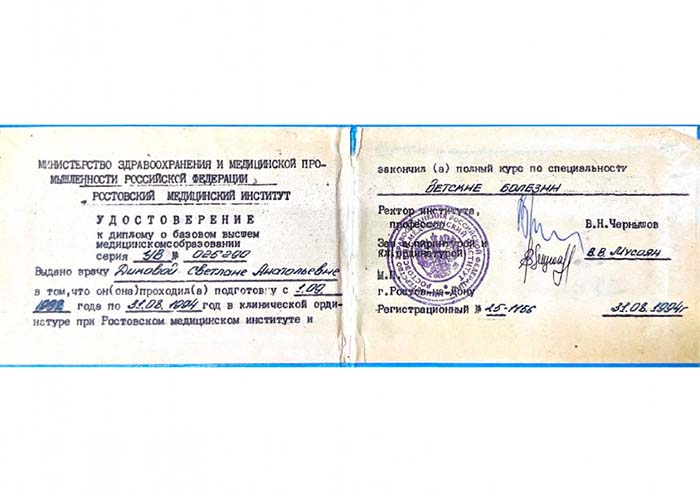

Лицензии и сертификаты нашей клиники

Медицинские услуги оказываются ООО "ЮгЭкоСервис+" по лицензии ЛО-61-01-008143 от 28.12.2021 г.